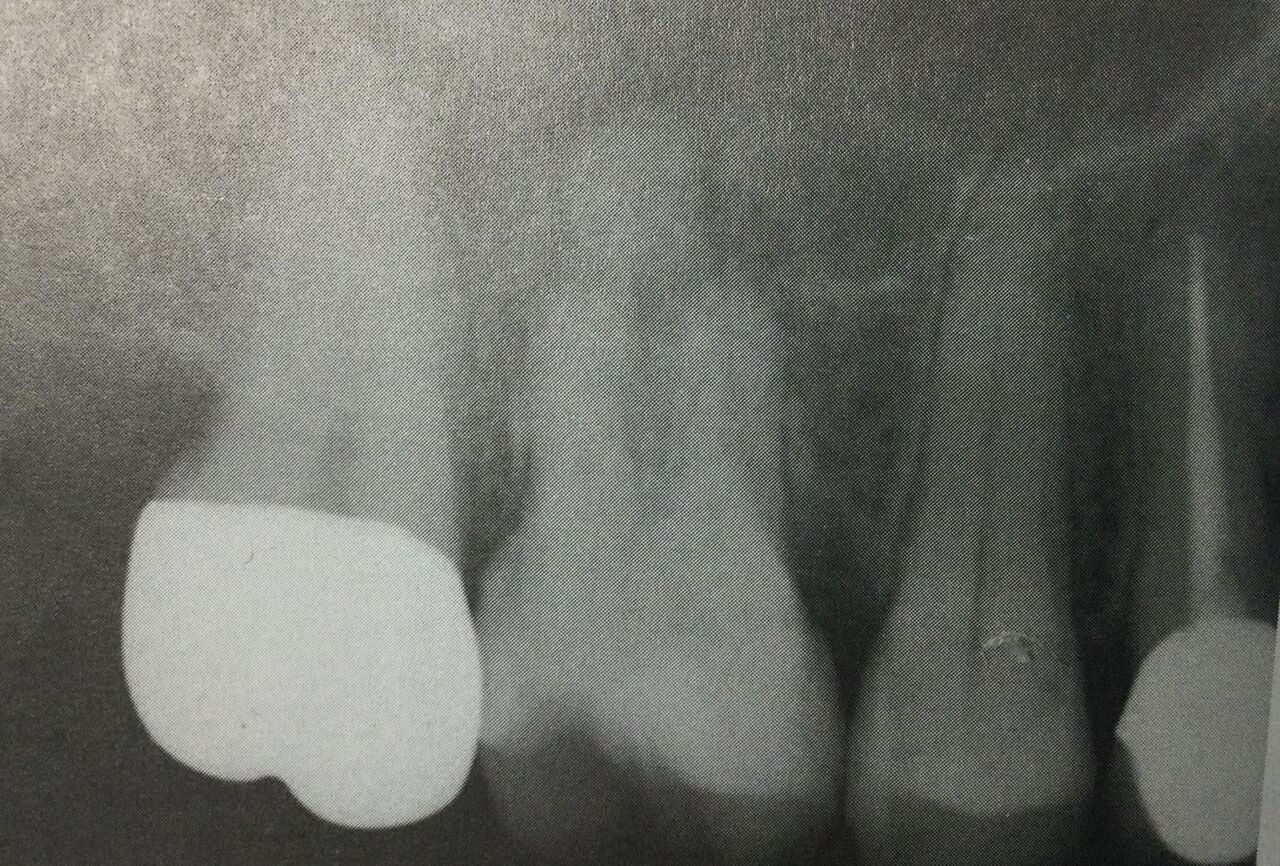

●歯周病の状態

歯の周りを歩く様に歯周ポケットを探って調べます。

ある所だけがスゴク深いポケットがある時には、

ヒビが入っていたり、

根っこのマタ、分かれ目に歯周病が進行していたり、

根っこに穴が開いてたり、

何か重大な問題が隠れているかもしれません。

全体的に深いポケットがある時には、歯周病が悪くなっているという意味なので歯を長く残せるのか?が問題です。

●被せる点で

最初に、被せて持たせられるのか、健康な歯の部分がどの位残っているのか?です。

被せるには、周りにグルッと健康な部分が2ミリ以上歯ぐきの上に残っていて欲しいです。